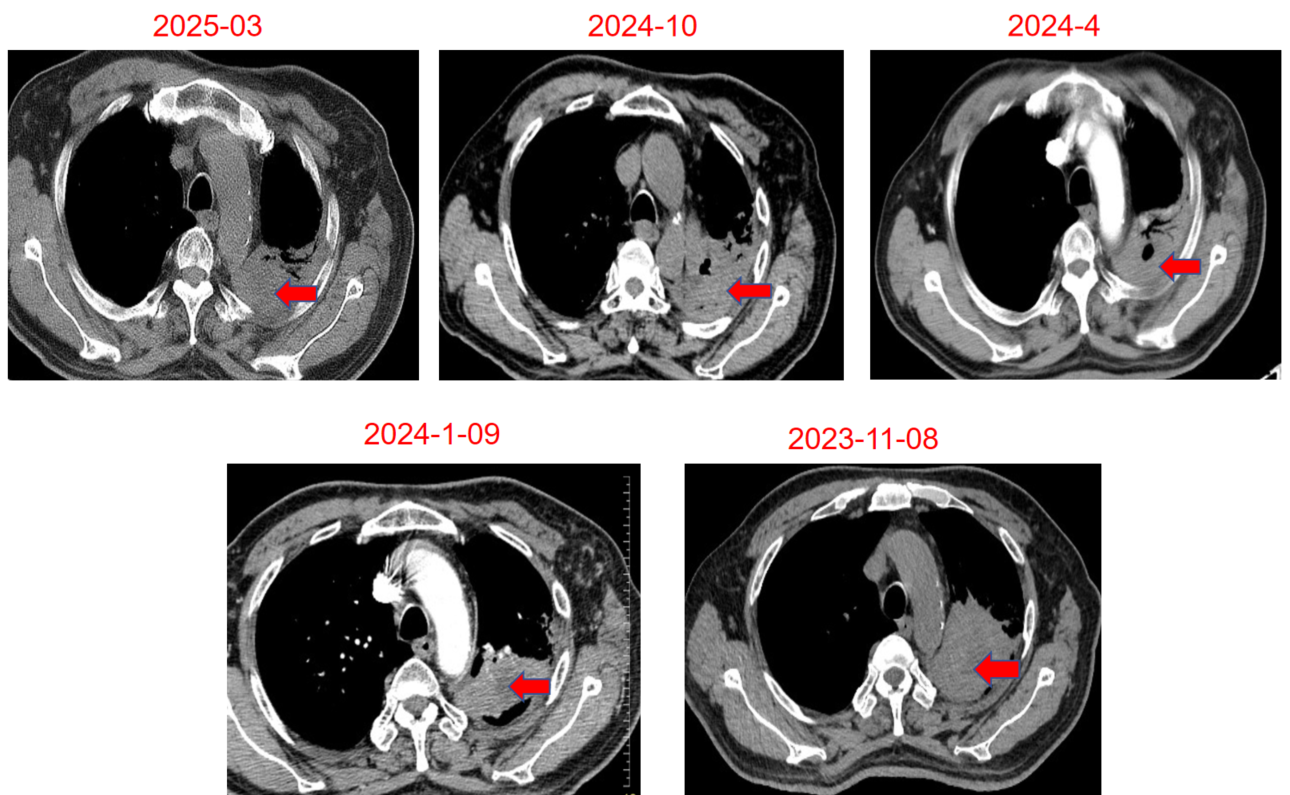

胸部CT(2022年11月):1、左肺上叶团块状软组织密度影并左肺上叶阻塞性炎症,左侧第3前肋骨质破坏,考虑肺癌,肿块较前减小,炎症较前吸收。2、纵隔及左侧肺门区多发淋巴结稍增大,部分钙化。完成2个周期治疗后,疗效评价为PR,随后继续该方案治疗2周期。

图片8.png

胸部CT(左:基线;右:2022年11月)

胸部CT(2023年1月):左肺上叶占位并周围阻塞性肺炎,肿块较前缩小,内新发小空洞,周围炎症较前吸收减少。疗效评价为PR。

2.png

胸部CT(左:基线;右:2023年1月)

胸部CT(2023年4月):左肺上叶占位并周围阻塞性肺炎,肿块较前稍缩小。疗效评价维持PR。

3.png

胸部CT(左:基线;右:2023年4月)